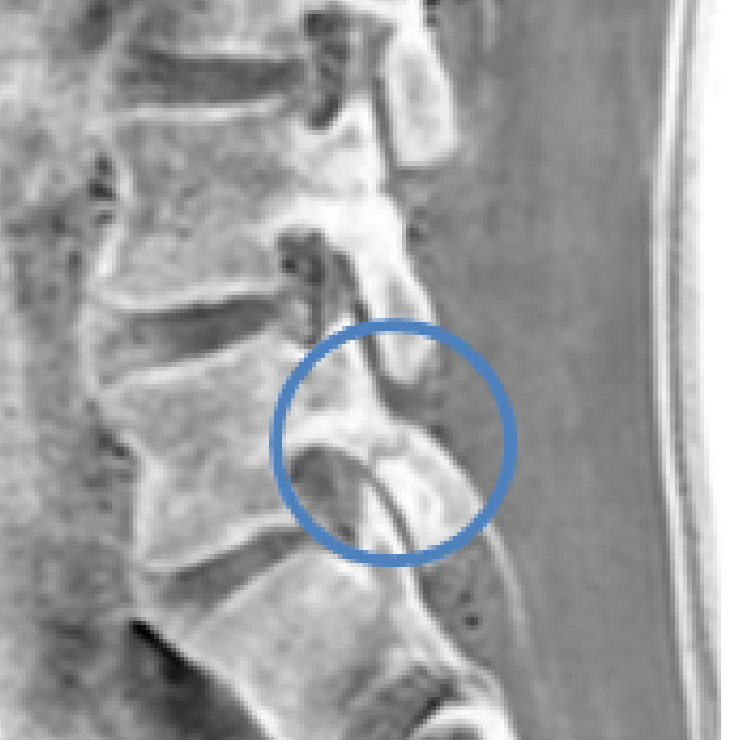

腰椎椎間板ヘルニアとは

腰椎に過度な前屈ストレスがかかり、椎間板内にある髄核が押し出されることをヘルニアと言います。

髄核が神経を圧迫すると様々な症状が出現します。

検査と診断の流れ

レントゲン・MRI・CT・ミエログラフィーによる画像所見と神経所見、感覚検査、筋力測定などを行います。